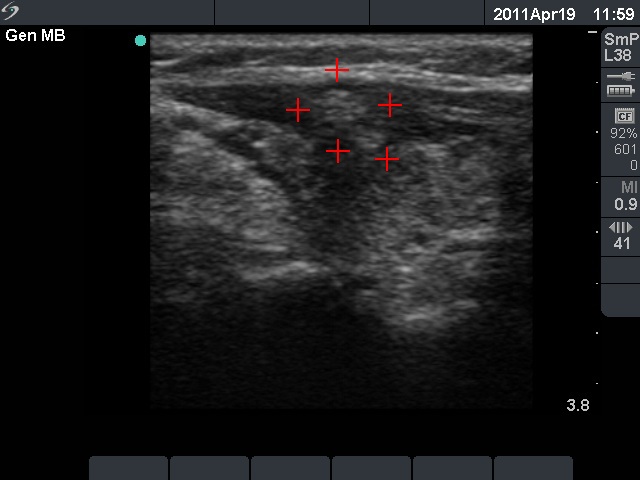

Granulation around surgical thread (cytological diagnosis) - case 1423

There is a relatively large echonormal tissue in the central part of the hypoechogenic mass. Note the acoustic shadowing. The lesion is avascular.